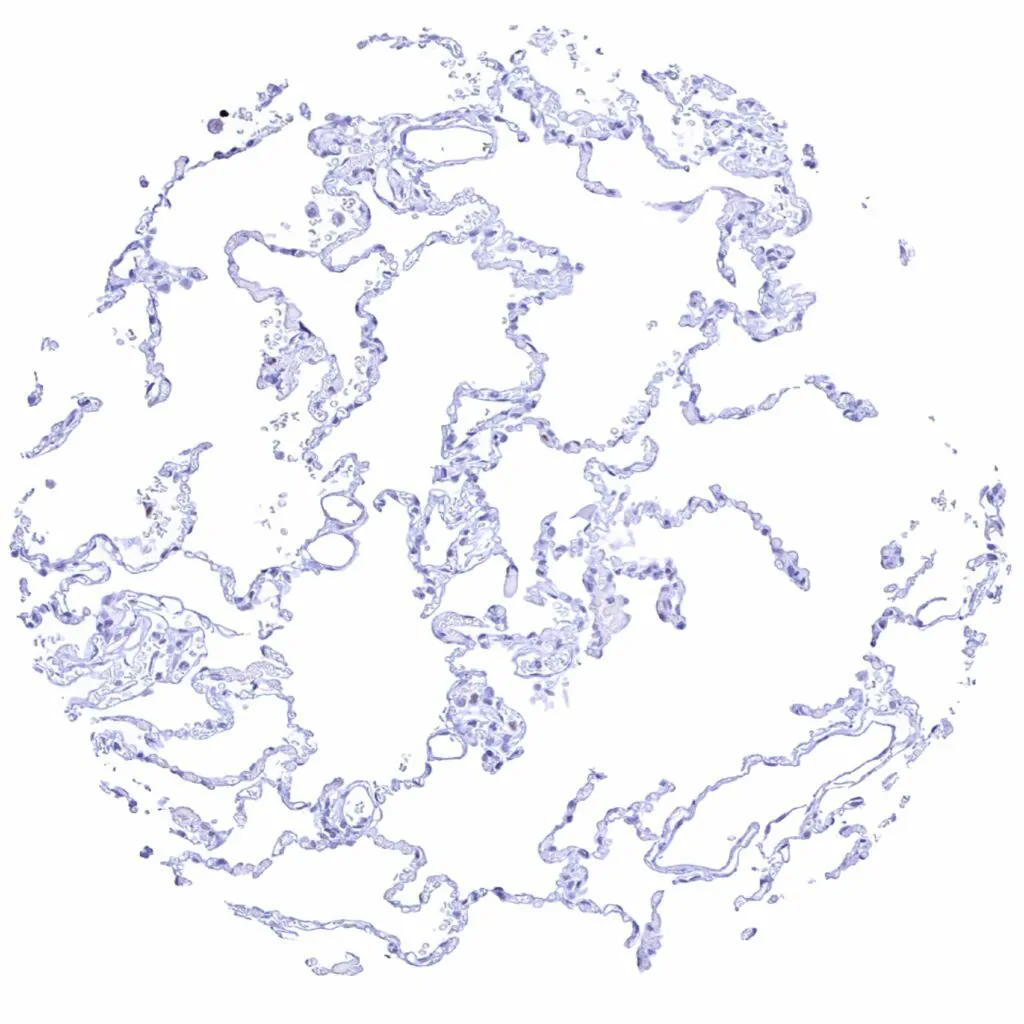

Lung